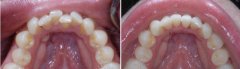

现在儿童错颌畸形的高发与家长们对口腔健康的错误认识和不重视有关,原因有...

随着生活条件提高,食物越来越精细化,孩子的牙齿就会因为缺乏应有的锻炼,...

经常接到类似的咨询,说孩子前牙比较不齐,应该属于拥挤那一类的,请问这种...